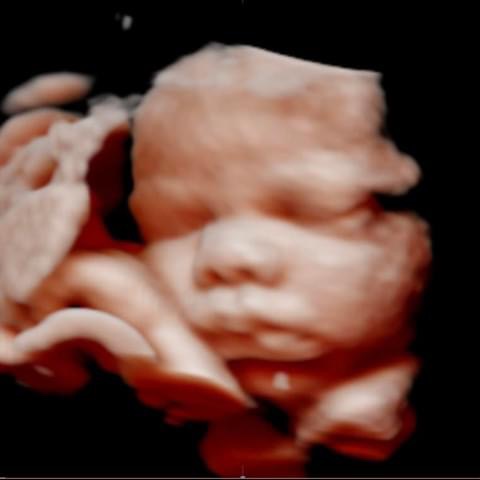

All photos are from our equipment and are of our actual clients.